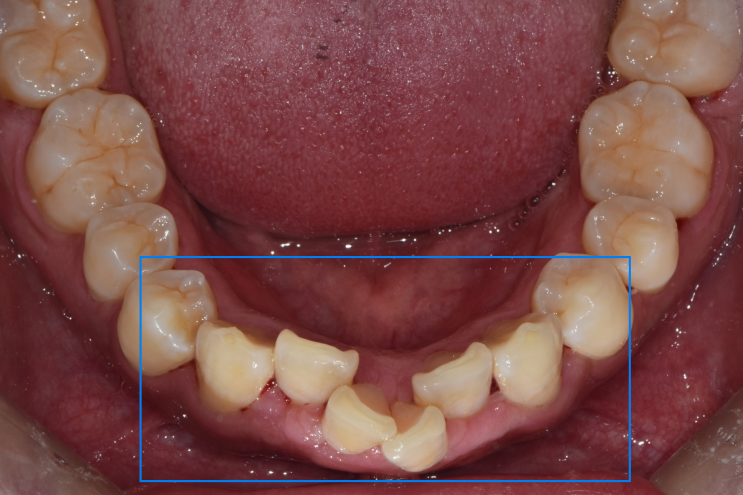

방화동교정치과, 덧니 치아교정 사례 살펴보기

방화동교정치과, 덧니 치아교정 사례 살펴보기 반갑습니다.^^ 로고스치과병원 대표원장 박희건입니다. &quo...